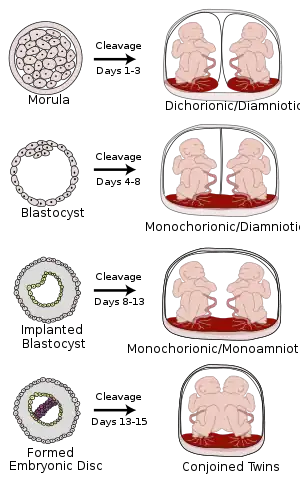

The degree of separation of the twins in utero depends on if and when they split into two zygotes. Dizygotic twins were always two zygotes. Monozygotic twins split into two zygotes at some time very early in the pregnancy. The timing of this separation determines the chorionicity (the number of placentae) and amniocity (the number of sacs) of the pregnancy. Dichorionic twins either never divided (i.e.: were dizygotic) or they divided within the first 4 days. Monoamnionic twins divide after the first week.

In very rare cases, twins become conjoined twins. Non-conjoined monozygotic twins form up to day 14 of embryonic development, but when twinning occurs after 14 days, the twins will likely be conjoined.[44] Furthermore, there can be various degrees of shared environment of twins in the womb, potentially leading to pregnancy complications.

It is a common misconception that two placentas automatically implies dizygotic twins, but if monozygotic twins separate early enough, the arrangement of sacs and placentas in utero is in fact indistinguishable from that of dizygotic twins.

| Dichorionic-Diamniotic | Normally, twins have two separate (di- being a numerical prefix for two) chorions and amniotic sacs, termed Dichorionic-Diamniotic or "DiDi". It occurs in almost all cases of dizygotic twins (except in very rare cases of fusion between their blastocysts[45]) and in 18–36%[46] (or around 25%[45]) of monozygotic (identical) twins.

DiDi twins have the lowest mortality risk at about 9 percent, although that is still significantly higher than that of singletons.[47] |

Dichorionic-Diamniotic twins form when splitting takes place by the third day after fertilization.[45] |

| Monochorionic-Diamniotic | Monochorionic twins share the same placenta.

Monochorionic twins generally have two amniotic sacs (called Monochorionic-Diamniotic "MoDi"), which occurs in 60–70% of the pregnancies with monozygotic twins,[46] and in 0.3% of all pregnancies.[48] Monochorionic-Diamniotic twins are almost always monozygotic, with a few exceptions where the blastocysts have fused.[45] Monochorionic twins share the same placenta, and thus have a risk of twin-to-twin transfusion syndrome. |

Days 4-8 |

| Monochorionic-Monoamniotic | Monochorionic twins share the same amnion in 1–2% of monozygotic twin pregnancies.[46]

Monoamniotic twins are always monozygotic.[49] The survival rate for monoamniotic twins is somewhere between 50%[49] and 60%.[50] Monoamniotic twins, as with diamniotic monochorionic twins, have a risk of twin-to-twin transfusion syndrome. Also, the two umbilical cords have an increased chance of being tangled around the babies. Because of this, there is an increased chance that the newborns may be miscarried or suffer from cerebral palsy due to lack of oxygen. |

Monoamniotic twins occur when the split takes place after the ninth day after fertilization.[45] |

| Conjoined twins |

When the division of the developing zygote into 2 embryos occurs, 99% of the time it is within 8 days of fertilization. Mortality is highest for conjoined twins due to the many complications resulting from shared organs. |

If the division of the zygote occurs later than the 12 days then conjoined twins are usually the result. |